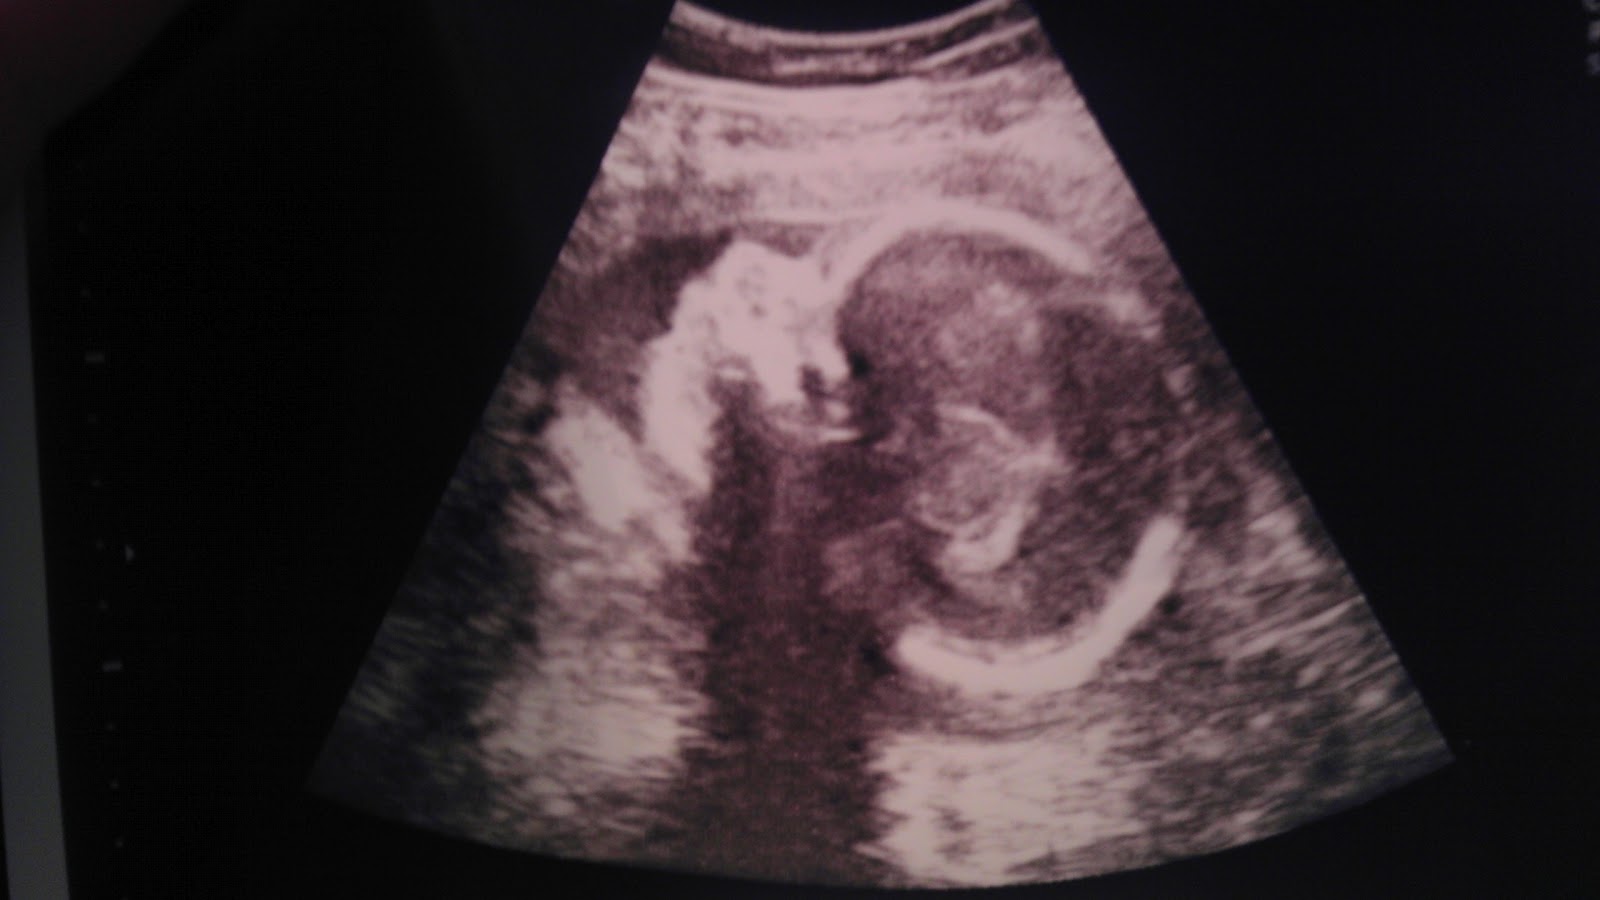

Today Matt and I met with CAFCA and with Dr. Sanjay Kaushal. At the first appointment with CAFCA we found that Adriana is now 2 pounds and 15 ounces. She is in the head down position (vertex), and is still doing some crazy movements in there! Steady growth and movement are a good sign.

Today Matt and I met with the doctors at the Center for Advanced Fetal Care and then soon after we met with Dr. Chaves (our pediatric cardiologist). Adriana is now 2 pounds and 2 ounces--she's gained a pound in 2.5 weeks! It's good to hear that she's growing steadily, and helps suppress some of our anxiety. Dr. Chaves also said that her heart has not changed. She is still convinced that Adriana will be perfectly fine for the first few months of her life. Most likely, she will not have to have a heart operation until she is an older infant. Dr. Chaves also thinks that she will only have to undergo relatively simple procedures as she grows. The specialists at UMMC will continue to monitor her growth and her dextrocardia as time goes on, since this such a rare condition. Her exact cardiac make up is not comparable with anyone else's, but we are confident that she is in good hands.